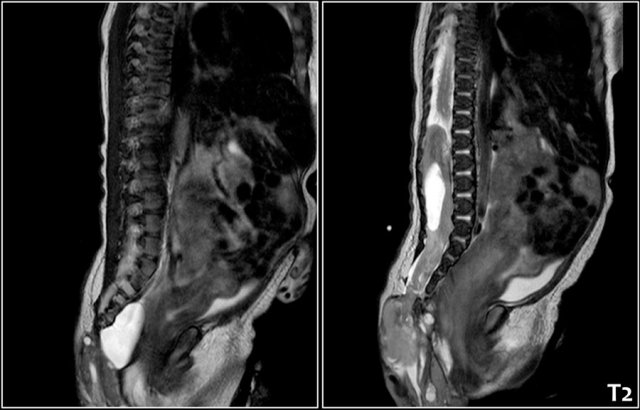

Two-year-old girl with a sacral mass. On ultrasound a cystic lesion anterior to the sacrum is seen, compatible with a class 4 sacrococcygeal teratoma. It was completely resected.

The intraspinal extension was visible on ultrasound, but MRI provides a better overview and a document for future comparison.

A parasagittal MRI shows a presacral cystic mass.

Newborn girl with a sacrococcygeal teratoma with external and internal solid and cystic parts, and a large intraspinal extension.